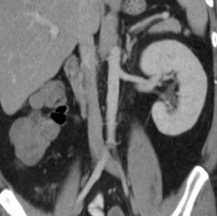

КТ, корональная реформация. Агенезия правой почки.

Подковообразная почка встречается чаще других и представляет собой увеличение одного из полюсов почки, в 90% - нижнего. Нередко меняется и положение подковообразной почки, которая может быть смещена медиально или даже на противоположную сторону. Подковообразная почка видна при любом виде исследования - внутривенной урографии , УЗИ, КТ, МРТ почек или сцинтиграфии.